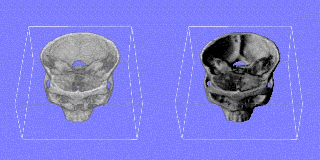

Interventional MR systems allow for a continuous monitoring of the brain typically in a plane through the tip of the intervention device. Whereas a microscope can see only the immediate neighbourhood, interventional MR can look ahead and to the sides which gives more information and security for planning the next step. As the quality and the number of slices generated by an interventional MR is worse than with the preoperative MR, there is a need for registrating and fusing the current slices of the interventional MR with the high quality reference scene.

upper: overview of scull with interventional device and associated scan plane; left: plane from interventional MRI scan (low quality); right: plane from preoperative MRI scan (high quality). Quicktime movie (180 KB) showing positioning of device. |